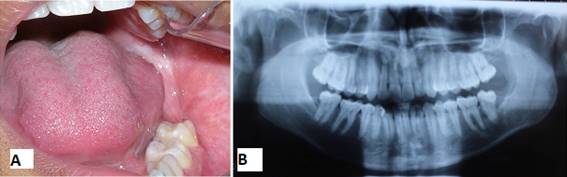

Un año después de la primera intervención, hubo una clínica y radiográficamente significativa reducción de la lesión (Figs 6 A y 6 B). Entonces se propuso realizar la enucleación de la cápsula remanente del quiste y de los elementos 38, 18, 28 y 48, bajo anestesia general.

Inicialmente se extrajeron los elementos dentales 18, 28 y 48 mediante técnica quirúrgica tradicional. Luego, se abordó el quiste restante a través de una incisión elipsoide a aproximadamente 0,5 cm de la abertura del área de descompresión. Tras la enucleación total de la cápsula quística remanente y el elemento 38 (Fig.7), se realizó el taponamiento de la cavidad con gasa con medicamento impregnada de forma similar a la utilizada en la primera intervención (Fig.8).

Se realizó el seguimiento del paciente clínica y radiográficamente cada 3 meses durante un período de un año y luego, anualmente, durante un período de cinco años. El aspecto clínico y radiográfico final con 5 años de evolución posoperatoria se puede apreciar en las Fig.10 A y Fig.10 B, donde se observa una completa neoformación ósea.